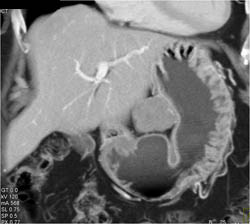

Delayed Gastric Emptying